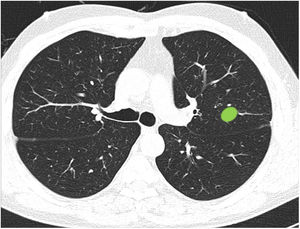

Capacidad para correctamente clasificar una lesión entre central y periférica en ausencia de líneas divisorias (fig. 3): en este bloque se valoró la capacidad de clasificar correctamente una lesión central (según una definición de centralidad [en los 2/3 internos] previamente establecida en el enunciado de la pregunta) en ausencia de líneas divisorias.

La mayoría de los participantes (78,6%) fueron capaces de catalogar una lesión central en ausencia de líneas divisorias (imagen 12), sin diferencias significativas entre especialidades (tabla 3). Del mismo modo, la edad, sexo o participación directa en el manejo de pacientes con cáncer de pulmón no influyeron en la respuesta a ninguna de las preguntas.

Capacidad de identificar correctamente un nódulo central en ausencia de líneas divisorias (imagen 12). La mayoría de los profesionales son capaces de identificar correctamente una lesión central (casillas en verde) en ausencia de las líneas divisorias sin que se observen diferencias significativas entre grupos